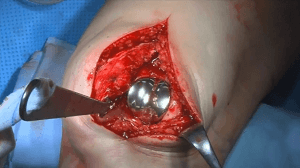

#032: All-Inside Meniskusrefixation mit Stryker A.I.R.

Operateur: Dirk Holsten, Philipp Niemeyer | Kommentar: Dirk Holsten

Provided by

Stryker

Date

Oct 2018

Format

TechTip

Price

0.99 €

Arthroscopy

Knee

Sports Medicine